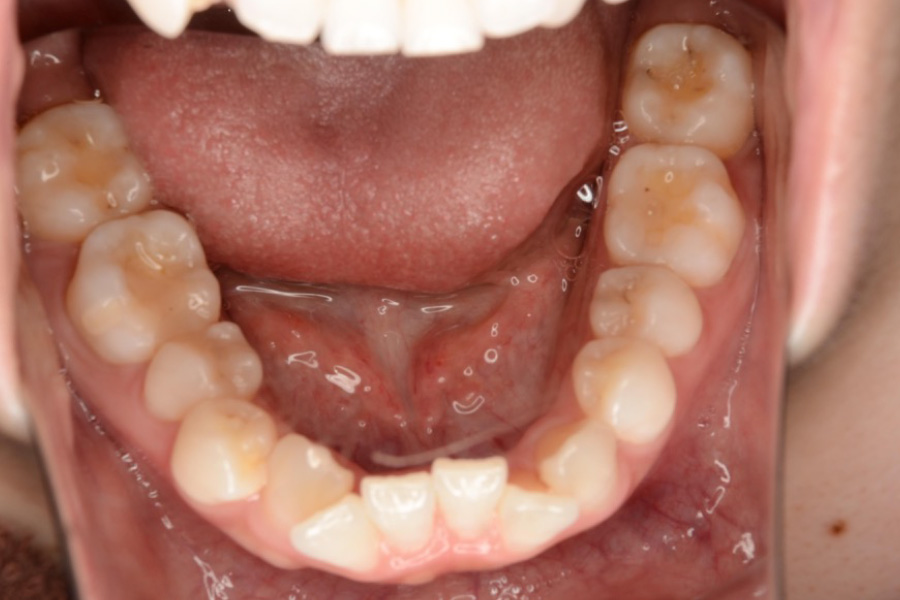

【20代女性】

八重歯、下の歯のガタつきを

インビザライン矯正で治療したケース

治療後

主訴 八重歯、下の歯のガタつきが気になる

治療内容 インビザライン矯正

小臼歯抜歯